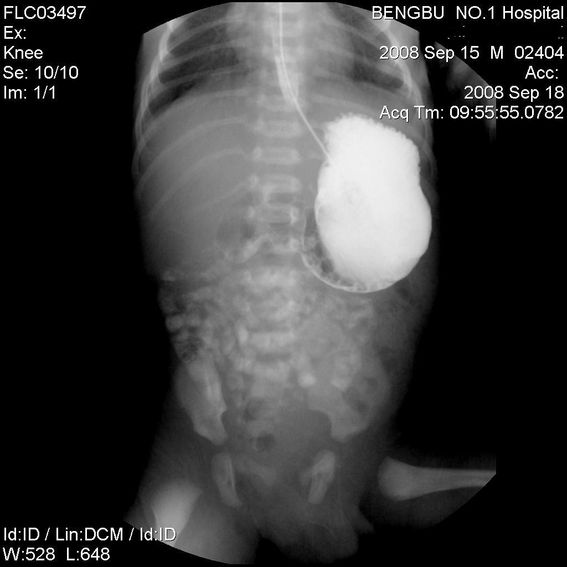

标题: PED1734:男,3天,以呕吐来诊。

十二指肠降部钡流不能顺利通过,胃及十二指肠球扩张。

考虑----十二指肠降部狭窄-----〔但这几个片子狭窄未能清楚显示,无法判断分型-----膜性或管状〕

考虑----十二指肠降部狭窄

十二指肠降部狭窄(可能为环状胰腺)。

十二指肠降部钡流不能顺利通过,胃及十二指肠球扩张,符合十二指肠降部狭窄

符合十二指肠降部狭窄或扭转不良.

考虑十二指肠降部狭窄.